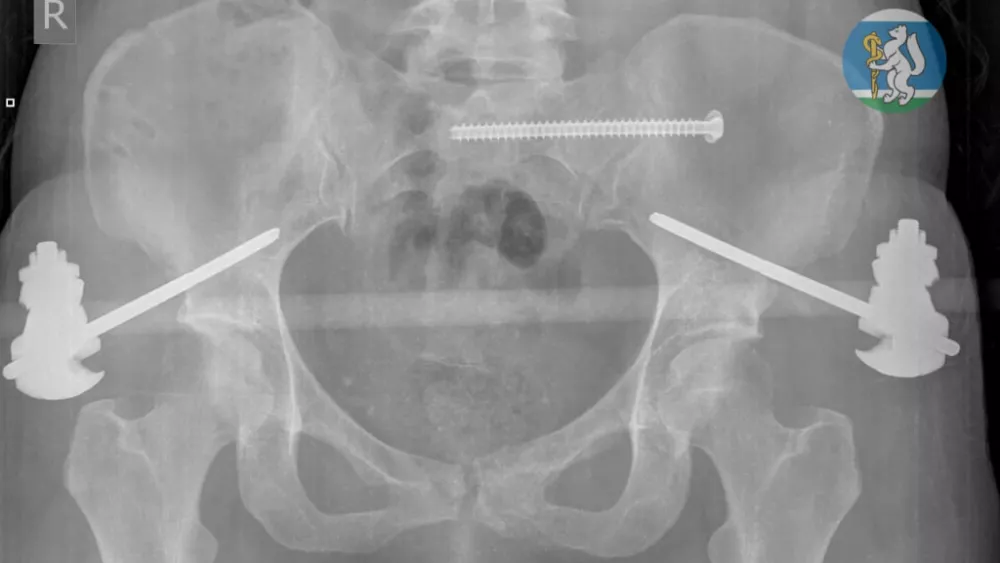

Диагнозы звучали как приговор: черепно-мозговая травма, повреждение шейного отдела позвоночника, множественные переломы костей таза, травма грудной клетки с повреждением лёгких, открытые оскольчатые переломы левой ноги. Большинство с такими травмами погибают ещё до приезда скорой.

Операция длилась несколько часов. Полторы недели в реанимации на ИВЛ, потом перевод в травматологию и ещё одна операция. Но врачи выбрали тактику ранней активации — и женщина снова начала двигаться. Через месяц её выписали в удовлетворительном состоянии. Сейчас она проходит реабилитацию.

Фото: Минздрав Свердловской области